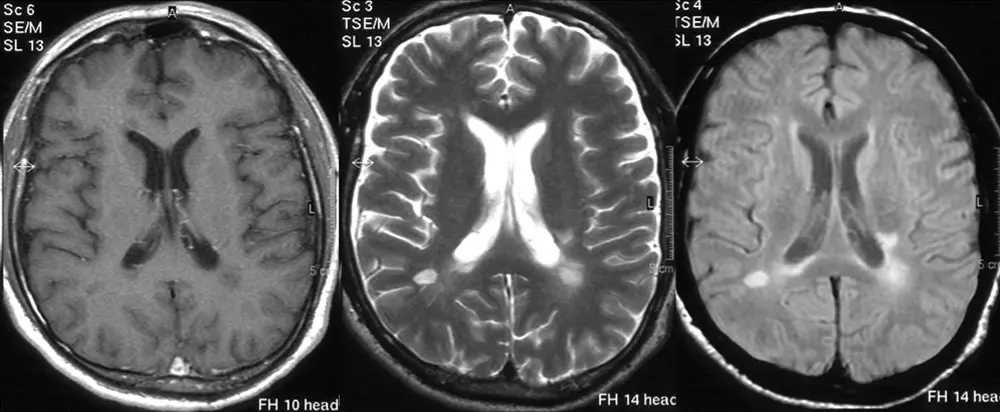

IRM

On pratique cet examen afin de vérifier la présence ou l’absence de métastases du cancer dans le cerveau.J’en ai passé 4 en un an.

De façon très simplifiée, l’idée est de reconstruire une image à partir des informations sur ‘l’orientation” (spin) des noyaux des atomes de la zone concernée quand ils sont soumis à un fort champ magnétique. On peut alors reconstruire des images en 3 dimensions, notamment avec des calculs mathématiques qui reposent sur les ondelettes, le même objet mathématique dont on se sert dans certains alogithmes de compression d’image.

On vous alonge sur une “planche”, puis, avant de commencer l’examen, on prépare une seringue contenant du gadolinium. un métal de la famille des lanthanides. Il n’est pas radioactif (enfin pas plus que le reste…). On l’utilise comme produit de contraste afin de produire des images plus détaillées.